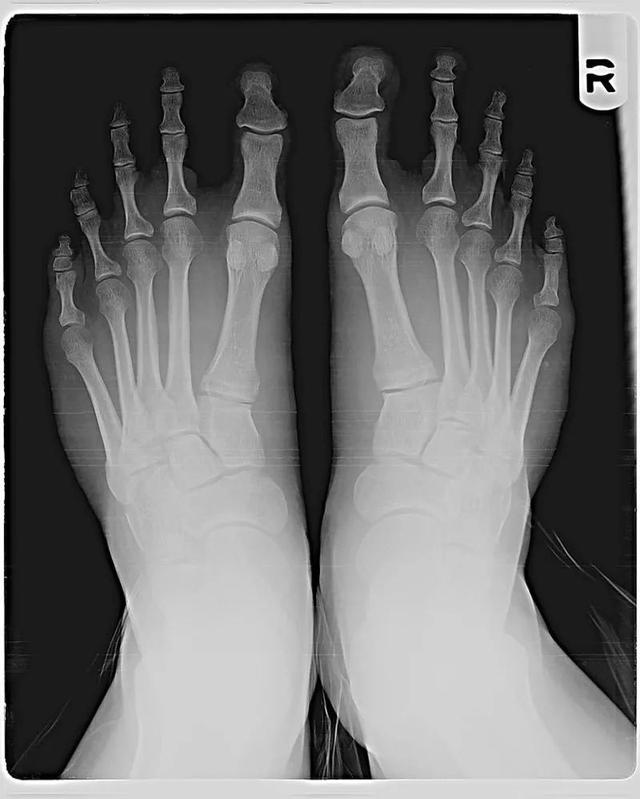

X光下的莫顿脚。图源:CJOTTAWA/CC BY-SA 3.0 大约有15%-20%的人长着莫顿脚。

造成莫顿脚的原因不是二脚趾长,而是大拇指的跖骨更短。